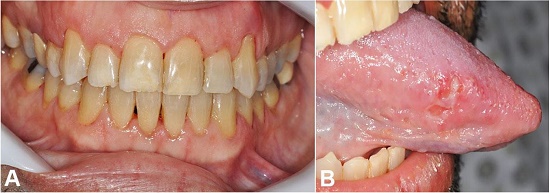

The cytogenetic analysis revealed a normal karyotype, and the panel of myeloid mutations by next-generation sequencing revealed mutations in FLT3, NPM1, and DNMT3 genes confirming the diagnosis of acute myeloid leukemia (AML). Daunorubicin (90 mg/m2) and cytarabine were given as induction chemotherapy. The patient had complete involution of the oral manifestations (gingival enlargement and the tongue ulcer) after 15 days of the first cycle of chemotherapy (Figure 4A and Figure 4B).